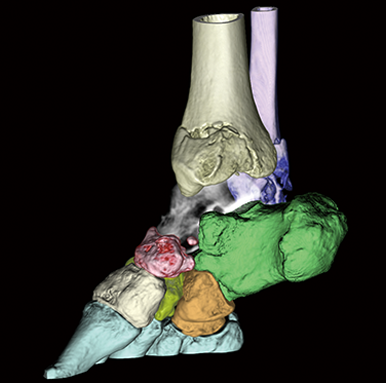

CT・MRIなどの断層画像から高精度な3D画像を描出し、解析を行う3D画像解析システム「SYNAPSE VINCENT Core」が、メディカルIT技術ブランド「REiLI(レイリ)」によるDeep Learningによって、さらなるバージョンアップを遂げました。膨大に蓄積された医用画像データを生かし、CTデータからの自動抽出機能や、脈管系の抽出機能が充実。画像認識技術を生かして、チーム医療を支え続けてきた富士フイルムだからこそ実現できた、AI時代の3D解析技術です。富士フイルムの「REiLI」が、チーム医療の最前線へと導きます。

「REiLI」によるDeep Learningを用いた臓器抽出で画像処理を簡単に行うことが可能です。

整形外科領域での抽出